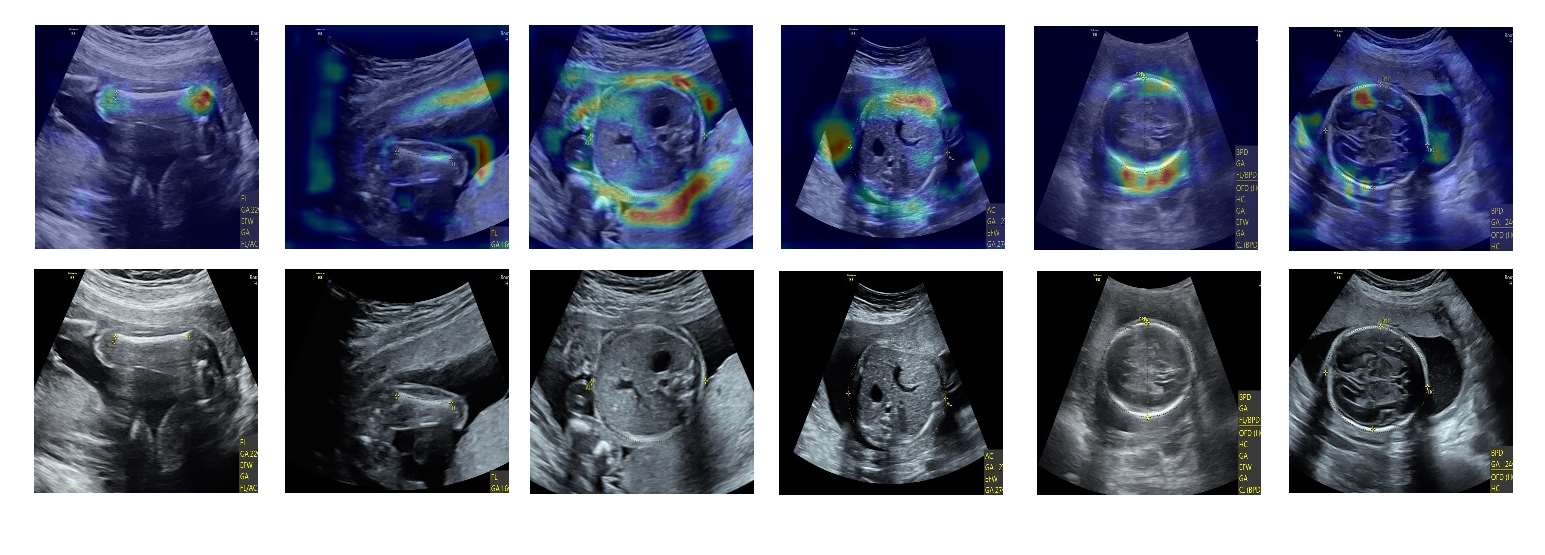

Although deep neural networks (DNN) have achieved state-of-the-art performance in various fields, some unexpected errors are often found in the neural network, which is very dangerous for some tasks requiring high reliability and high security. The non-transparency and unexplainably of Convolutional Neural Networks (CNN) still limit its application in many fields, such as medical care and finance. Despite current studies that have been committed to visualizing the decision process of DNN, most of these methods focus on the low level and do not take into account the prior knowledge of medicine. In this work, we propose an interpretable framework based on key medical concepts, enabling CNN to explain from the perspective of doctors' cognition. We propose an interpretable automatic recognition framework for the ultrasonic standard plane, which uses a concept-based graph convolutional neural network to construct the relationships between key medical concepts, to obtain an interpretation consistent with a doctor's cognition. Extensive experiments have empirically shown that our model can meaningfully explain the decision of the classifier and provide quantitative support.